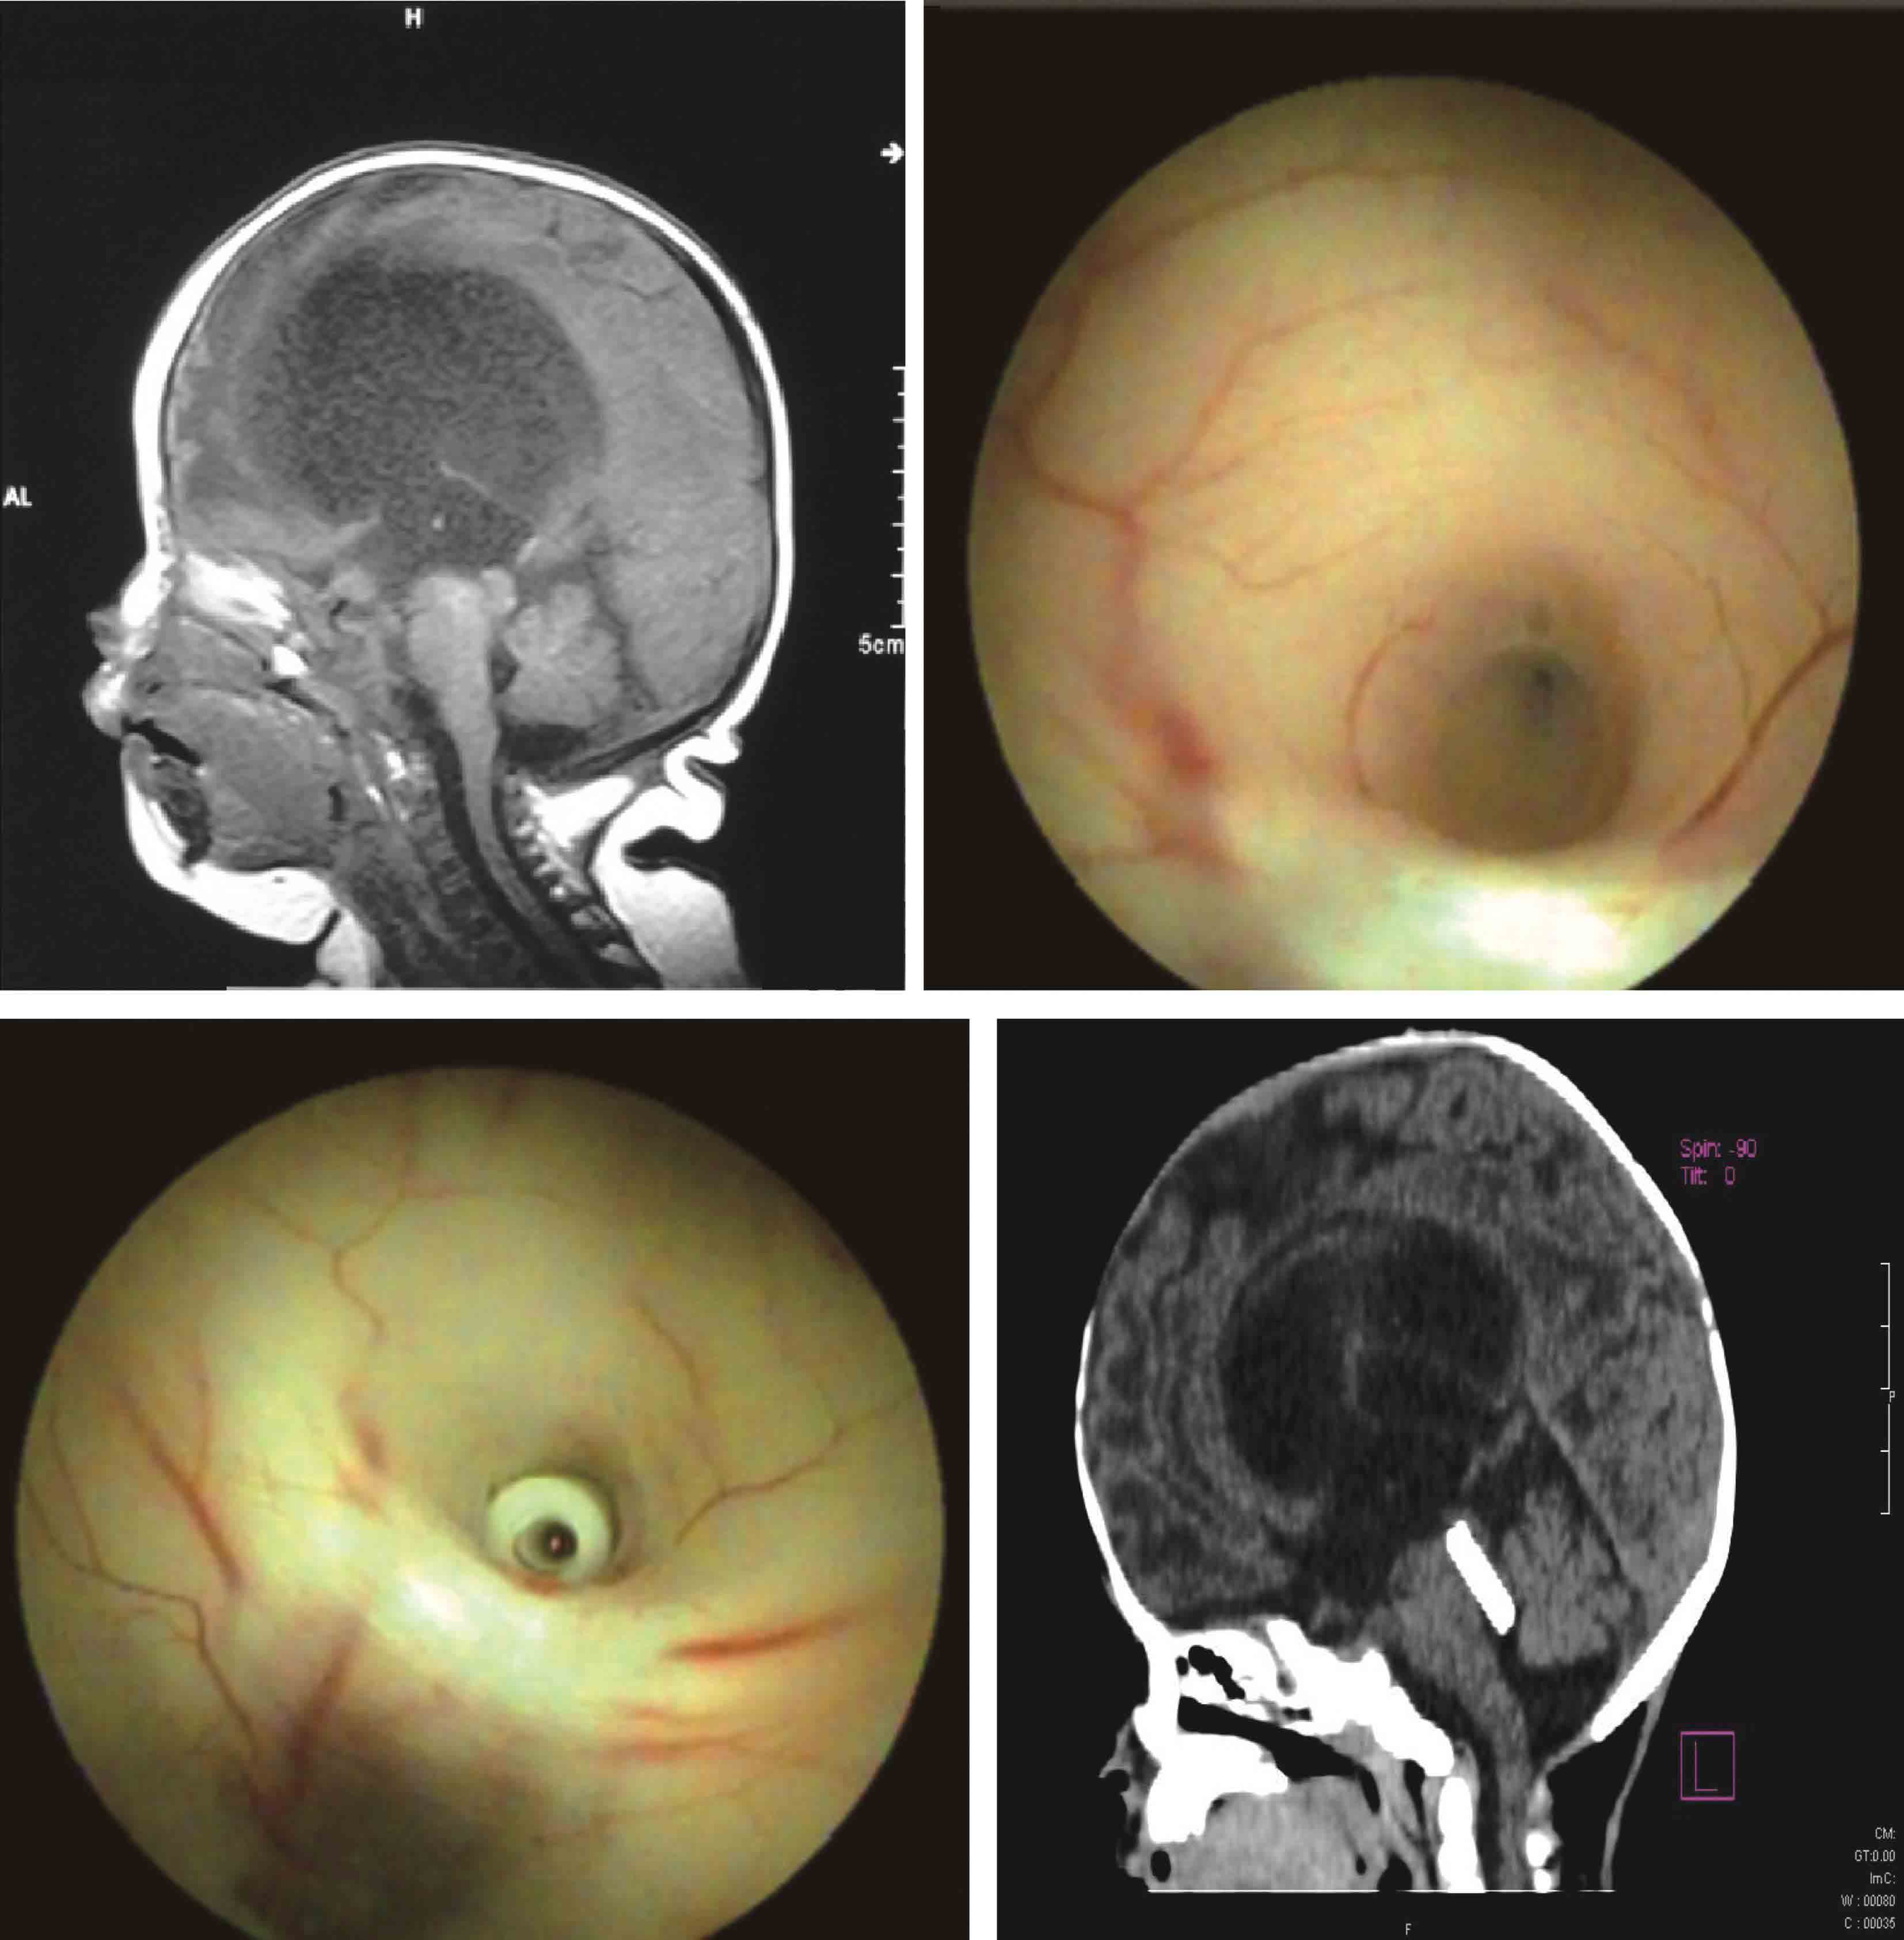

图3-1-2-11 脑积水合并Chiari畸形

a.术前MRI矢状位片示脑积水,小脑扁桃体下疝;b.第三脑室底造瘘术后1周,MRI矢状位片示小脑扁桃体下疝减轻